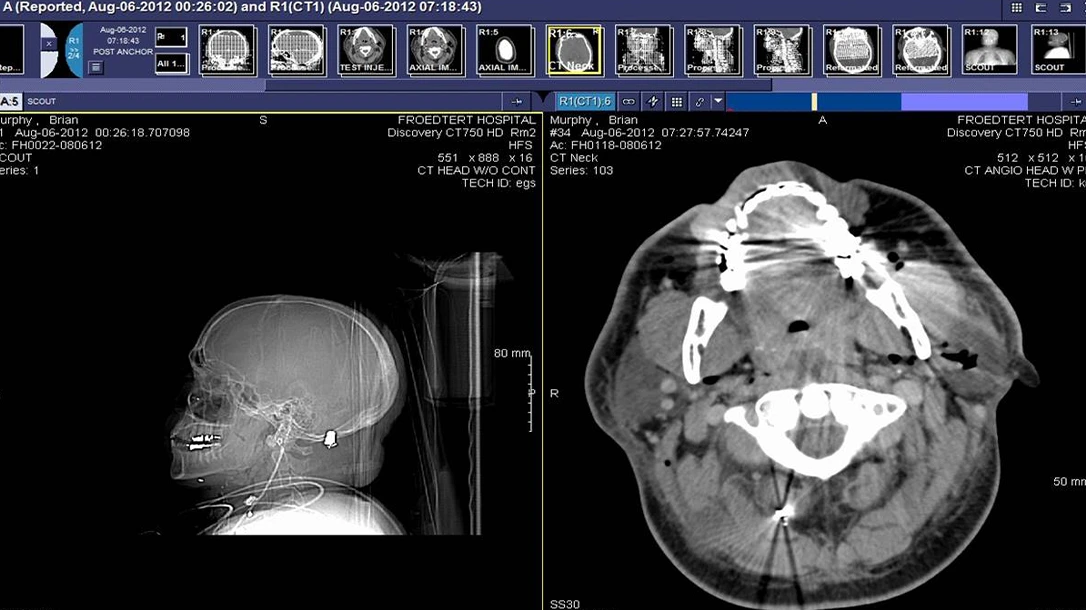

As soon as Lt. Murphy exited his vehicle, the shooter ran outside to confront him. They both fired simultaneously, but unfortunately the killer’s bullet found its mark. Shot in the face, Lt. Murphy took cover behind a car, temporarily losing sight of the target. Knowing he was still in the fight and needed to act, Murphy stood back up to locate the shooter. The killer had outflanked him, though, and mercilessly fired more rounds into the wounded officer.

Lt. Murphy continued to fight with what little strength he had left until another officer arrived at the scene and started drawing fire away from his wounded partner. Eventually, the crazed man took his own life and ended the bloodbath.

As Murphy was transported to the hospital, his chances of survival looked dim. Many of the shots hit his extremities, and some had been aimed toward his vital organs. What saved Lt. Murphy’s life was his Armor Express ballistic vest. None of the rounds penetrated his chest, and now this hero has a second chance at life due to proper self protection.

Lt. Murphy: The only time that I felt in trouble was when the last shot hit me in the back of my skull. My head felt like it exploded and I was knocked flat. It took me a few minutes to regain my bearings and crawl out to where the other officers could see me.

Lt. Murphy: I was hit in the chest, the side and the upper back; fortunately for me, the vest worked perfectly. No rounds entered the vest. As a matter of fact, the last round — the one that went into my skull — skipped off the vest due to its trajectory and the curvature of the armor around my shoulder and back. That round skipped under the first and second sheets of material for only two inches, but even that small amount slowed its velocity enough that my skull wasn’t fully penetrated. Those two inches of material saved my life.